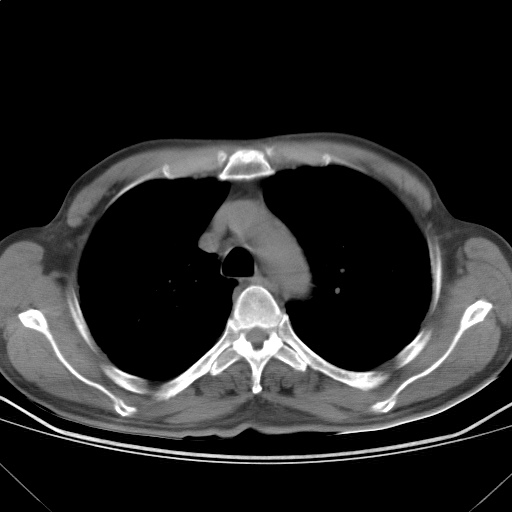

以下是引用随光逐影在2009-5-1 13:53:00的发言:[br]考虑为:1)两肺血行播散型肺结核;2)右肺下叶炎症感染。3)右侧胸膜增厚。